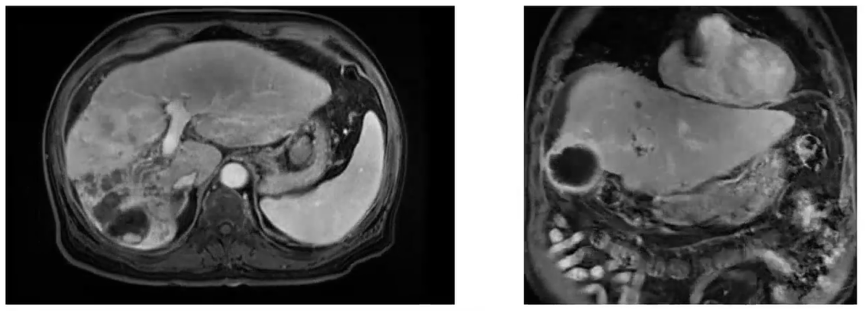

2021年12月30日MR示,左肝肿瘤较前明显缩小为71mm,肝内转移较前缩小,癌栓较前缩小。

图4. 2021年12月30日MR与既往MR比较

治疗前及治疗4程后的肝动脉造影显示,右肝肿瘤血供较前减少,且范围缩小。但在S4段仍存子灶血供。因此在此程治疗中针对该子灶进行了单独的栓塞化疗。肿瘤标志物显著下降,疗效评价PR(mRECIST)。

2022年1月28日腹部MR提示,肝右叶肿瘤出现较明显的缺血坏死和缩小,肝右叶转移病灶同样较前明显缩小(图6)。肿瘤标志物AFP(-)(图7);疗效评价PR(mRECIST)。患者体能状态好;瑞戈非尼减量至80mg qd 后不良反应缓解。

图6. 2022年1月28日腹部MR